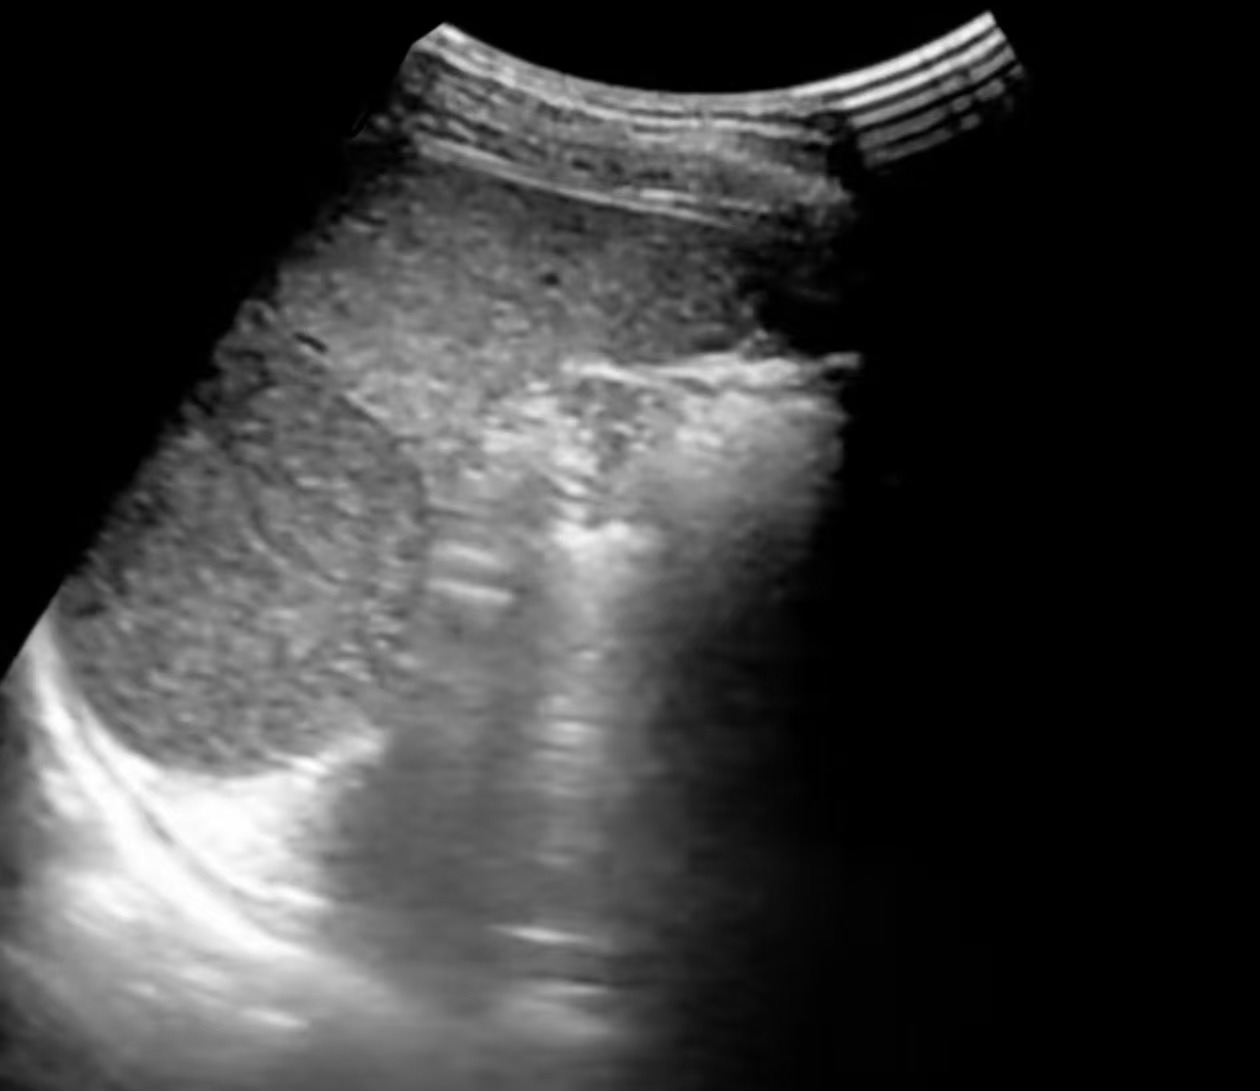

超声检查:首选的“影像侦察兵”

超声因其无创、便捷、无辐射、实时动态、价格低廉的优势,成为脾脏筛查和复查的首选影像学方法。它通过声波反射成像,可以清晰地显示脾脏的形态、大小以及内部结构。

脾血管瘤的“超声肖像”:

常见类型与表现

脾血管瘤在超声下的“长相”并非千篇一律,主要可分为三种经典类型,超声医生正是通过这些特征来进行判断:

• 超声描述:脾实质内出现一个或多个边界清晰的明亮团块(回声高于周围正常的脾组织),像夜空中的星星。

• 内部特征:内部回声均匀或呈细网格状,后方回声无明显变化或略有增强。

• 血流信号:彩色多普勒超声下,多数未见明显血流信号或仅见周边点状血流。这是因为血管瘤内血流速度极其缓慢。

• 这是最典型、最经典的脾血管瘤表现,诊断信心较高。